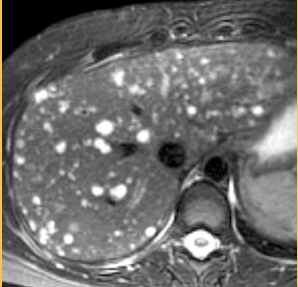

How can cirrhotic regenerative nodules be differentiated from malignant neoplastic lesions on MRI?

T1 weighted: variable signal intensity but they do not show early arterial enhancement unlike hepatocellular carcinoma. T2 weighted: May be hypo-intense (siderotic nodules), isointense but not hyperintense unlike most liver metastases and dysplastic nodules.